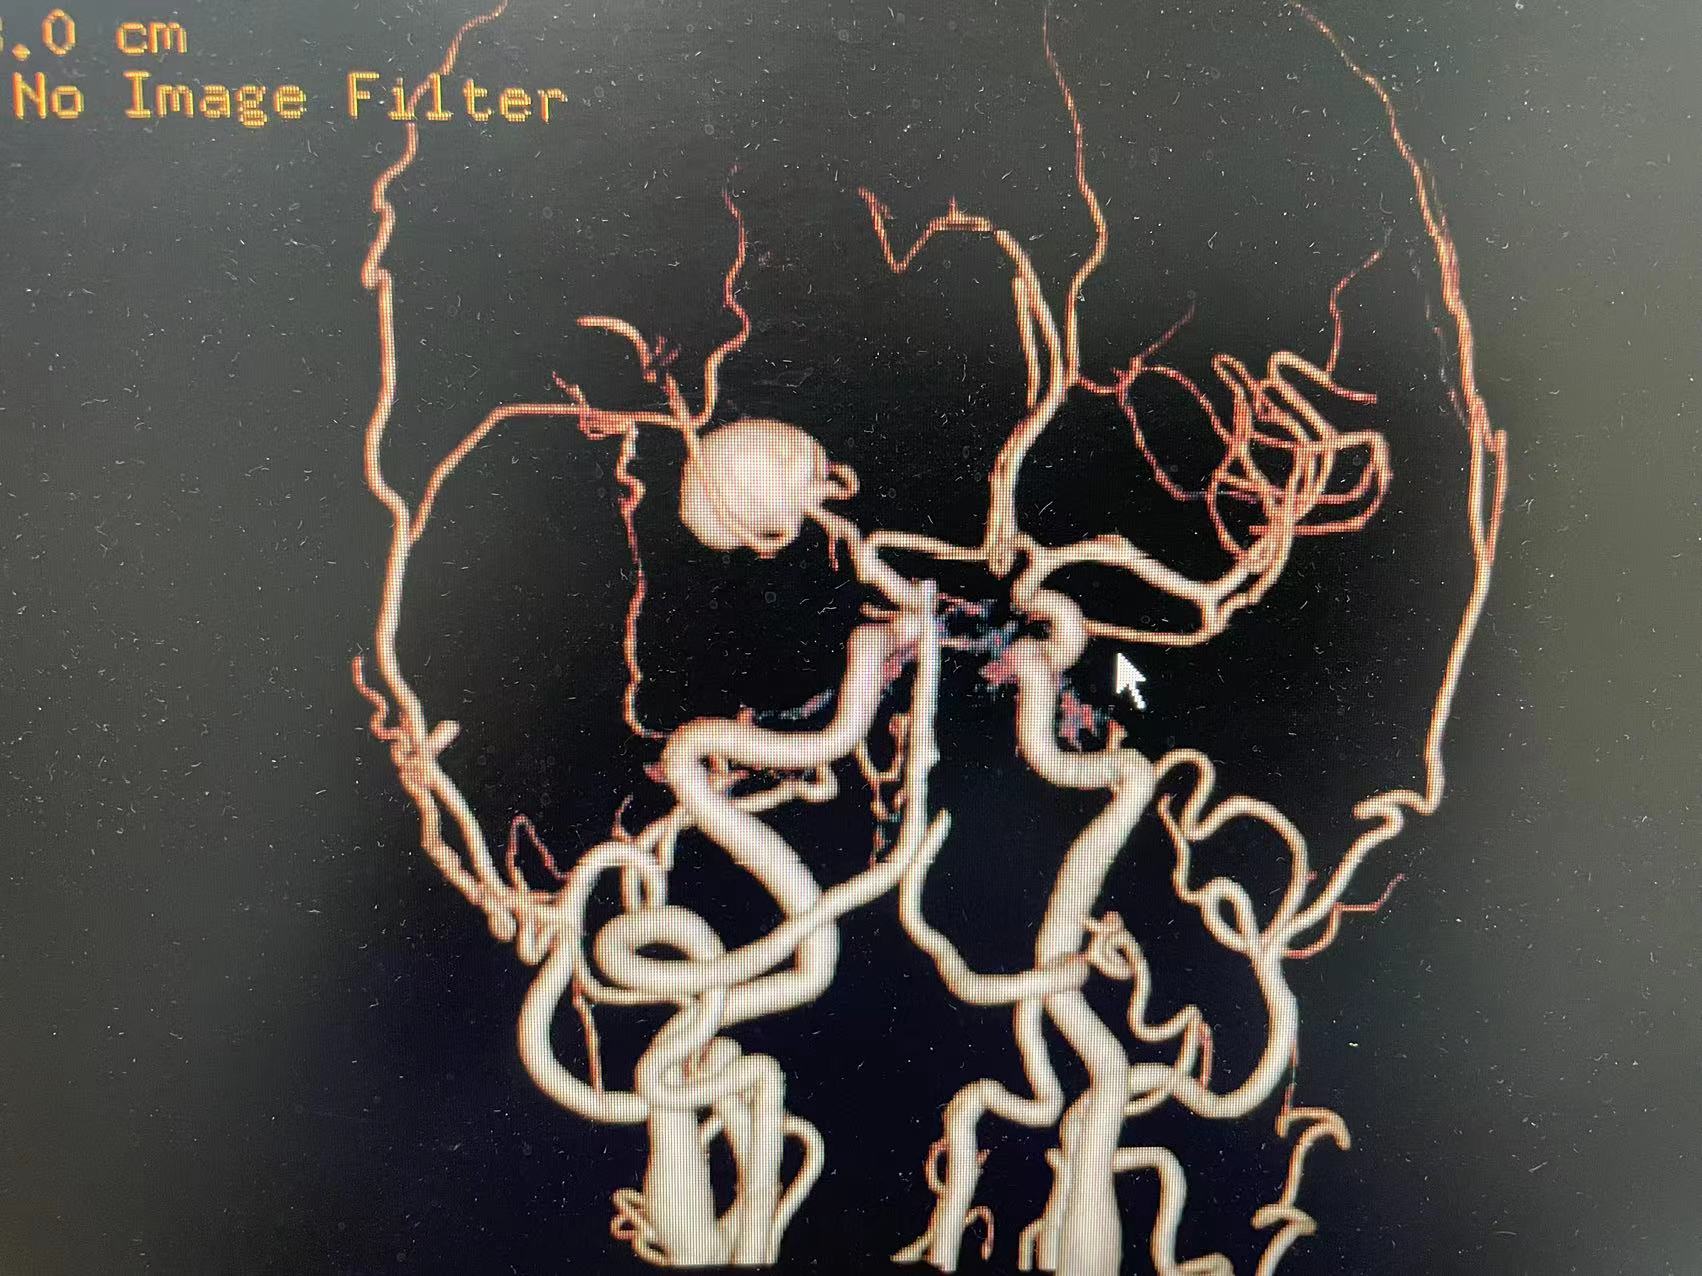

HRQ、女,66岁,463177,因头昏头疼2天,吐词不清1天于20230203日16时24分入院。右侧肢体肌力四级。

指导手术者:成都中医药大学附属医院神经外科主任李定君教授。

夹闭术后两个月,出院后一个月!再次出血,血肿量大,患者清醒!转上级市级医院,拟予介入栓塞后清除血肿

家属选择保守治疗,患者一直清醒!两个月前在华西行介入栓塞术,血肿吸收!

介入栓塞术后两个月来复查!患者清醒轮椅而来,言语稍含糊,右侧下肢肌力可大于三级,上肢一级!